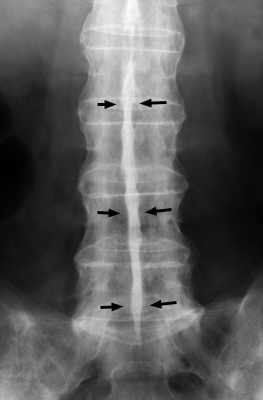

Single frontal radiograph of the lumbar spine in a patient with bony fusion of the adjacent lumbar vertebrae with syndesmophyte formation, characteristic for ankylosing spondylitis. In addition, there is a linear increased density running along the spinous processes. The dagger sign is a single central radiodense line on frontal radiographs related to ossification of supraspinous and interspinous ligaments.

AP Spine - Click on the image for a larger version